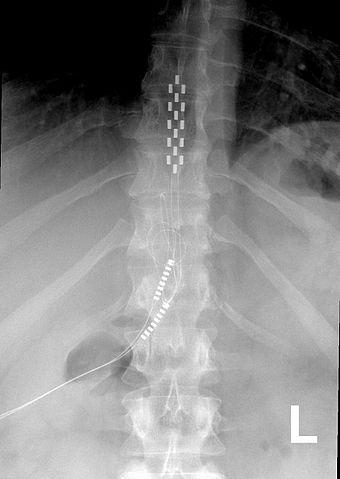

Global Spinal Cord Stimulator Market Report Analysis By Top Key Players Like Medtronic, St Jude, Stimwave, Cyberonics, NeuroPace And Global Forecast 2018-2025

Spinal Cord Stimulator Market Research Report is a professional and in-depth study on the current state which focuses on the major drivers and restraints for the key players. Spinal Cord Stimulator Industry research report provides granular analysis of the market share, segmentation, revenue forecasts and geographic regions of the market.